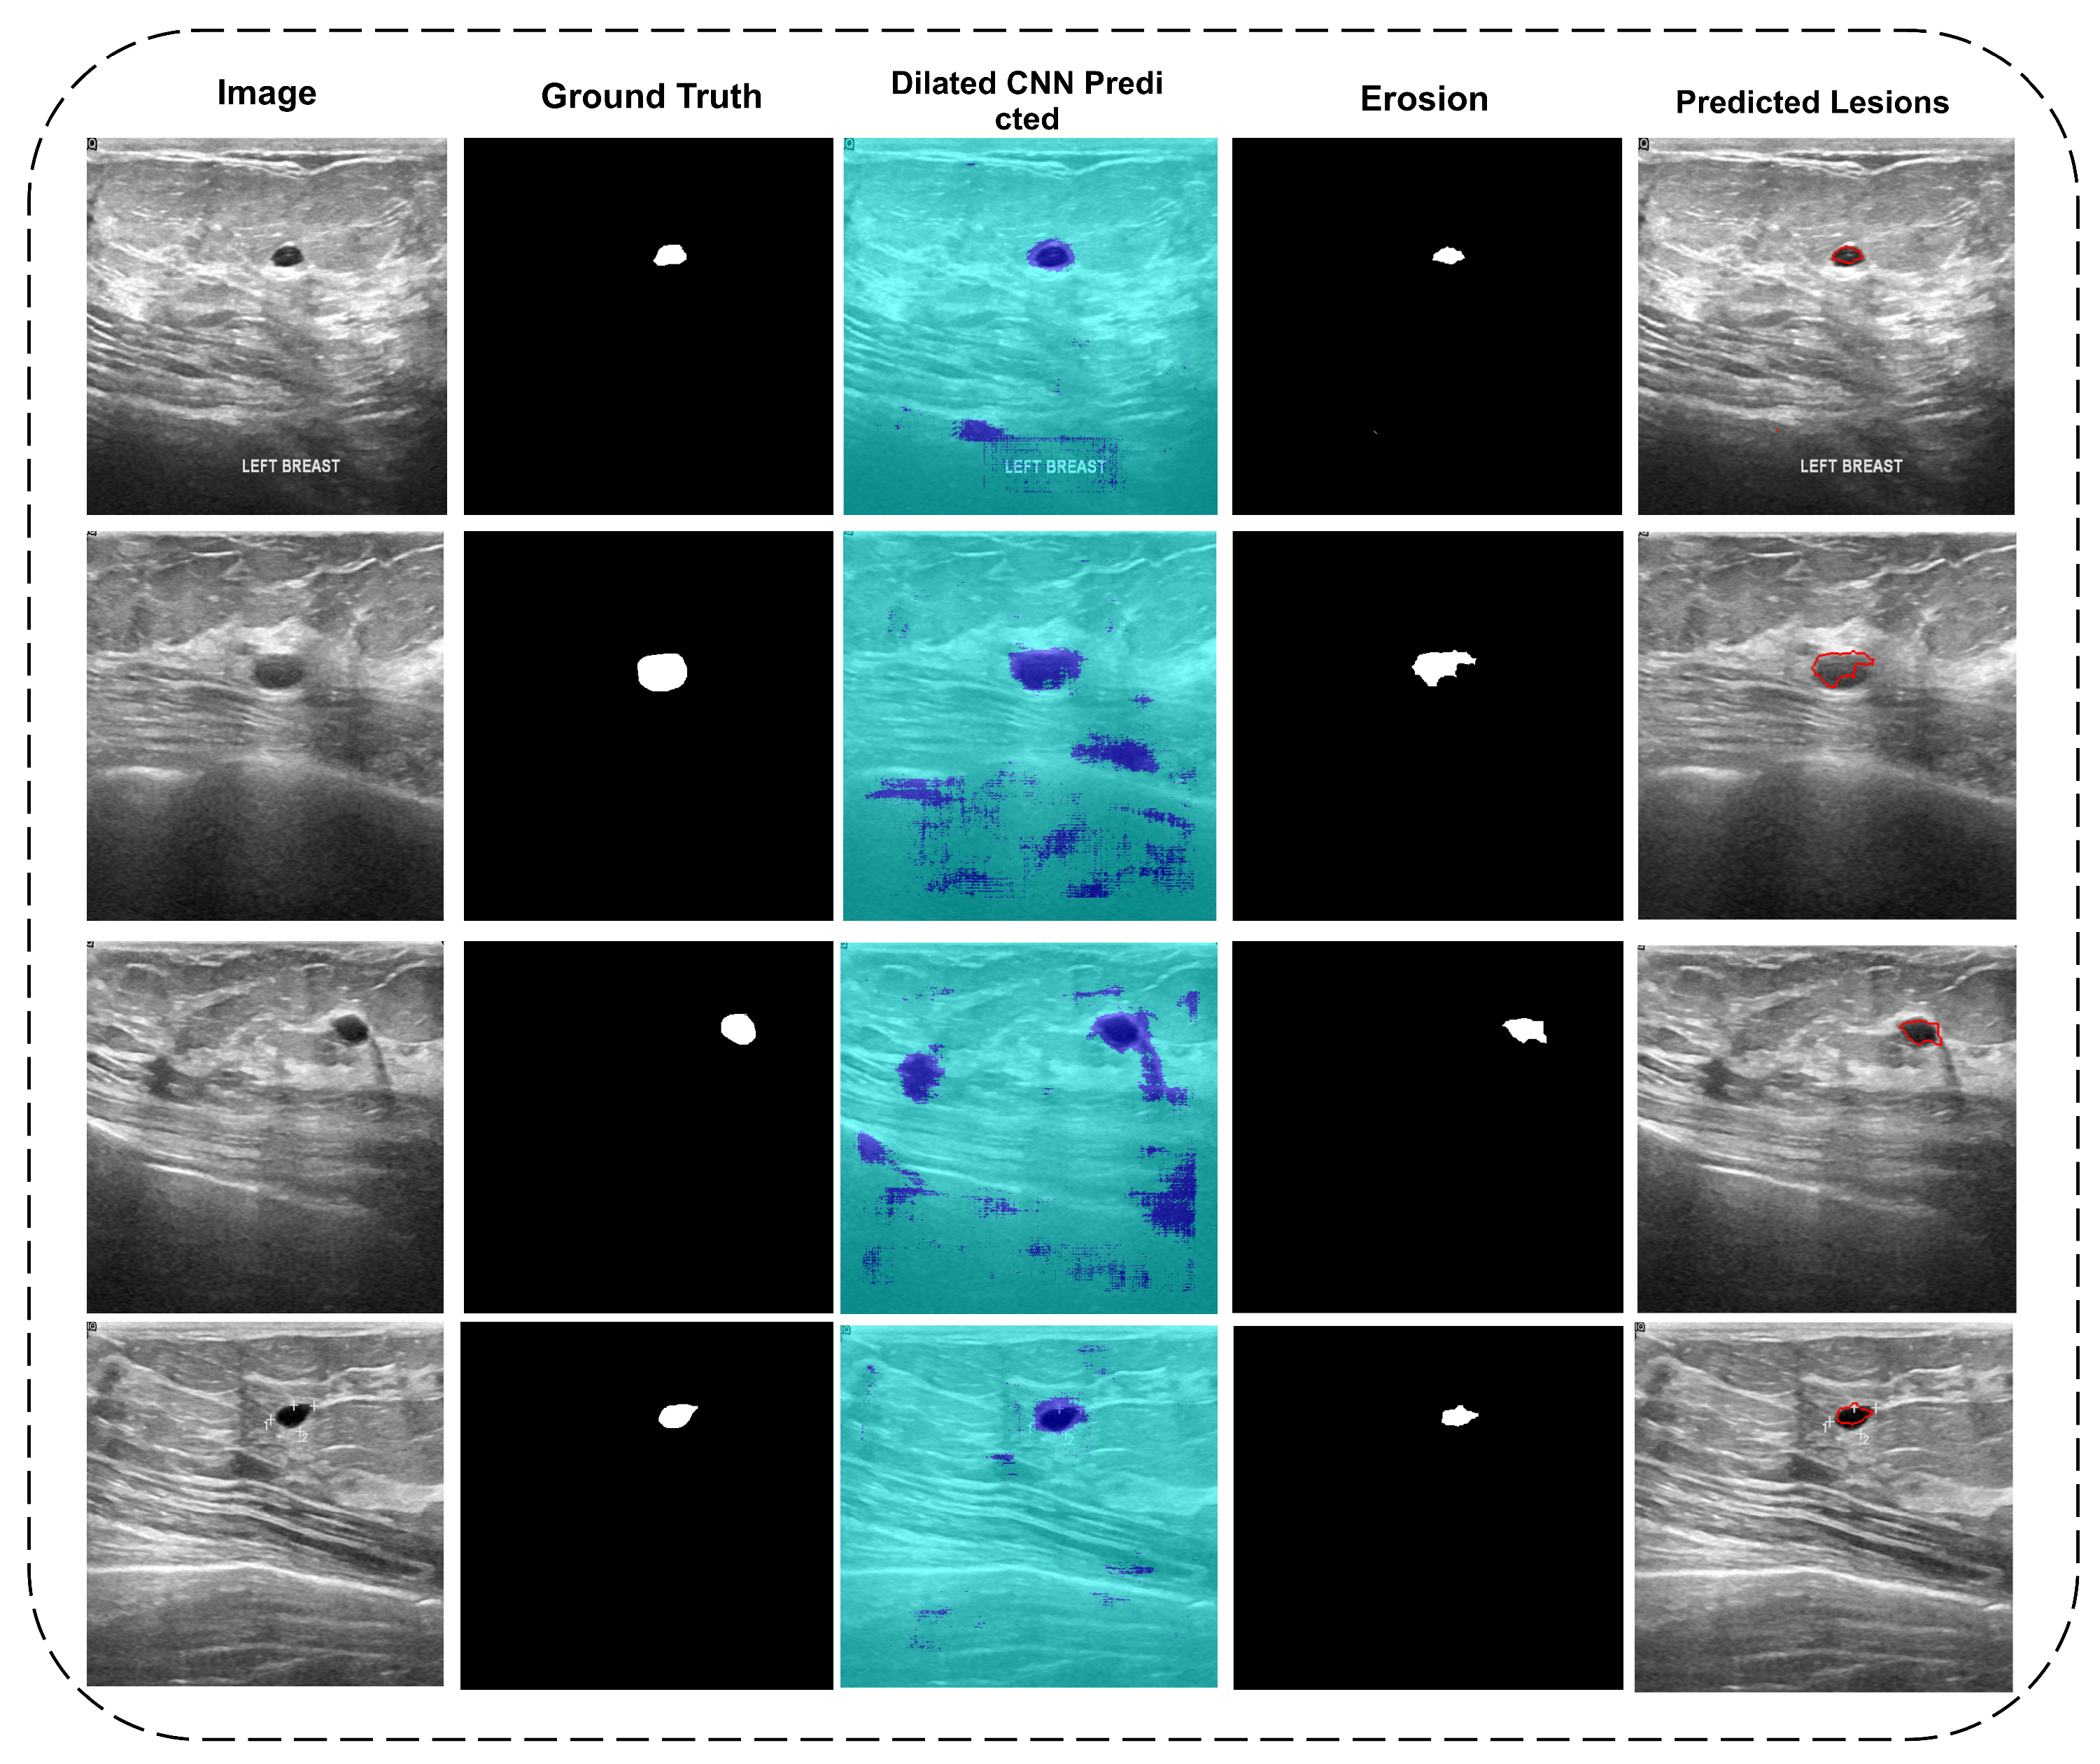

3.1. Segmentation

3.1.1. Dilated Semantic Convolutional Neural Network

3.1.2. Erosion

4.1. Di-CNN Evaluation